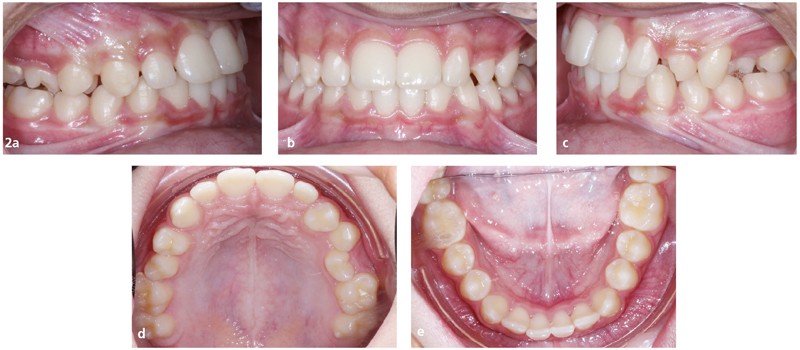

Paulo D., 13 ans, consulte pour un motif esthétique. Il présente une ligne du sourire non harmonieuse, avec la rotation de 24 en place de 23, un sourire gingival à droite et les milieux incisifs non alignés entre eux (fig. 1).

Sur le plan occlusal et dentaire, on observe une classe III molaire et canine à gauche, une proalvéolie maxillaire, une occlusion inversée au niveau des 15/46 et 25/35-36, une non concordance des milieux incisifs et une transposition complète de 23 et 24 (fig. 2 et 3).